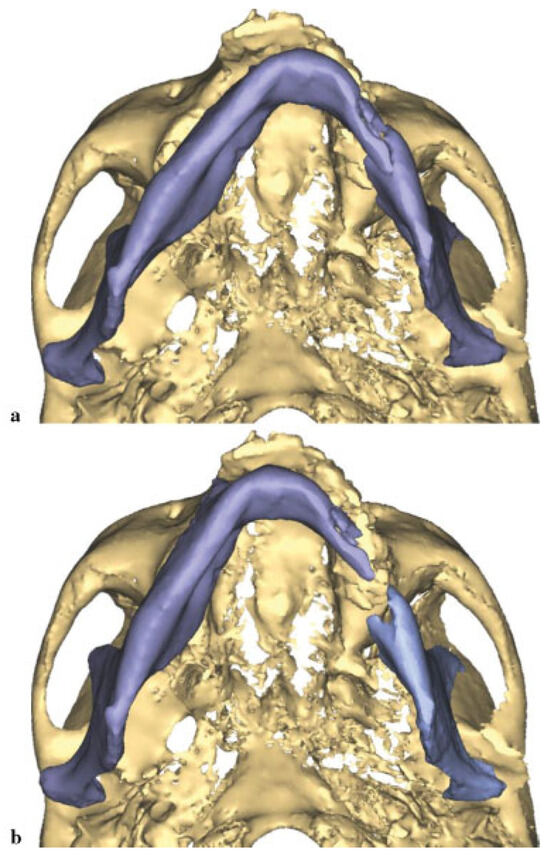

Owing to the significant injury to the anterior and posterior column of the cervical spine, a fusion was performed of C5–T1. Prior to surgery, he was kept in a cervical spine collar. To minimize the time in the operating room (OR) and manipulation of the displaced, atrophic mandible, his initial CT scans were used to fabricate a model to facilitate the correction of the complex mandible fracture. Turnaround time was 5 days. Using three-dimensional (3D) software for VSP (Materialize, Plymouth, MI), the midline of the larger segment of the mandible was aligned with the midline of the maxilla (Figure 2a,b). A mirror image was created using the opposing uninjured mandibular body (Figure 3a,b). A stereo-lithographic model was fabricated facilitating the preoperative bending of a 2.5-mm reconstruction plate, based on the virtually planned model (Figure 4). The plate was contoured to the model the evening before surgery.

Figure 2. (a) Preoperative submental image prior to manipulation. (b) Midline of mandible aligned with midline of the maxilla.